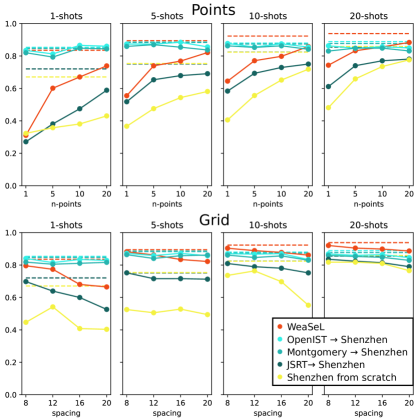

As mentioned in the paper, the results for Montgomery and Shenzhen lungs segmentation task, had results similar to the OpenIST dataset, as can be seen in tables 1 and 2, and in Figure 1. So the same conclusions from the paper holds for these datasets: From Scratch being the worst baseline, Fine Tuning from similar domains providing the best results, while WeaSeL reaching comparable results to the Fine-Tuning baselines with more data samples.

From Scratch From JSRT From OpenIST From Montgomery WeaSeL Points Points Points Points Points Shot 1 5 10 20 1 5 10 20 1 5 10 20 1 5 10 20 1 5 10 20 1 32.26 35.75 38.07 43.05 27.11 38.09 47.46 58.88 83.42 81.27 86.57 86.03 81.99 79.33 84.82 84.37 53.40 59.86 71.58 74.80 5 36.66 47.53 54.35 58.12 51.78 65.35 67.90 69.09 87.35 87.31 88.46 85.61 85.90 86.96 85.42 83.70 68.91 82.97 81.78 81.26 10 40.57 55.62 65.17 71.85 58.36 69.33 72.92 75.01 87.74 85.51 87.51 85.48 86.24 85.29 86.26 84.14 69.82 80.57 82.58 83.00 20 48.14 65.88 73.50 77.62 61.15 74.01 77.04 78.09 86.31 84.70 85.74 84.94 83.03 84.82 84.84 83.10 71.44 80.71 82.39 82.78 Grid Grid Grid Grid Grid Shot 8 12 16 20 8 12 16 20 8 12 16 20 8 12 16 20 8 12 16 20 1 44.67 54.18 40.81 40.35 69.78 63.92 59.97 52.63 84.05 81.50 83.45 82.83 81.79 80.50 81.07 81.65 79.90 76.85 75.89 78.63 5 52.53 50.58 52.81 49.43 75.19 71.59 71.60 71.26 87.24 85.85 87.21 85.73 86.40 84.06 85.74 86.14 82.88 83.59 83.18 79.72 10 73.60 76.38 69.71 55.20 80.92 78.97 78.04 75.16 86.99 86.71 87.01 83.39 86.12 84.64 85.63 82.96 85.53 84.09 82.85 80.97 20 81.76 81.77 80.97 76.54 83.56 82.37 81.43 79.00 86.86 85.94 86.40 84.55 85.91 85.26 84.76 82.88 86.93 86.33 85.73 84.11